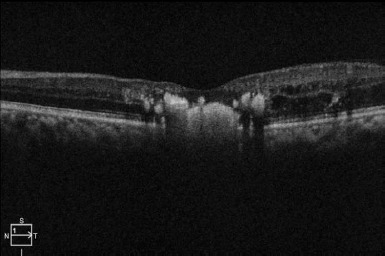

成人柯茨病是一种不常见的危及视力的疾病,其特征是视网膜上出现异常血管。科茨病常见于出生后头十年的儿童,但极少见于出生后第三个十年以后的成年人,或以单侧视力丧失为特征的成年人。尽管这是一种威胁视力的疾病,但其病因仍未确定,各种遗传和血管异常都与此病有关。诊断主要依靠眼科检查、眼底照相、荧光素血管造影术和光学相干断层扫描。治疗方法包括激光光凝、玻璃体内注射抗血管内皮生长因子制剂,晚期病例需要手术干预,治疗的目的是避免视网膜脱离和新生血管性青光眼等并发症,而这些并发症在成人型高兹病中相对罕见。尽管在治疗方面取得了进展,但预后却不尽相同,有些患者会出现严重的视力障碍。这篇综述概述了成人柯茨病的临床特征、诊断、管理和预后,强调了早期发现和干预对优化视力预后的重要性。

Adult-onset Coats disease is an uncommon and vision-threatening disease characterized by the development of abnormal blood vessels in the retina. Coats' disease commonly affects children in the first decade of life, but very rarely manifests in adults after the third decade of life, or who characteristically present with unilateral vision loss. Despite being a sight-threatening disease, the etiology remains inconclusive and various genetic and vascular abnormalities are implicated. Diagnosis relies on ophthalmologic examination, fundus photography, fluorescein angiography, and optical coherence tomography. Treatment modalities include laser photocoagulation, intravitreal injections of anti-vascular endothelial growth factor agents, and, in advanced cases, surgical interventions are needed and the treatment is aimed at avoiding complications like retinal detachment and neovascular glaucoma, which were comparatively rare in adult-onset Coats' disease. Despite therapeutic advancements, the prognosis varies, with some patients experiencing significant visual impairment. This review outlines the clinical features, diagnosis, management, and prognosis of adult-onset Coats' disease, underscoring the importance of early detection and intervention in optimizing visual outcomes.